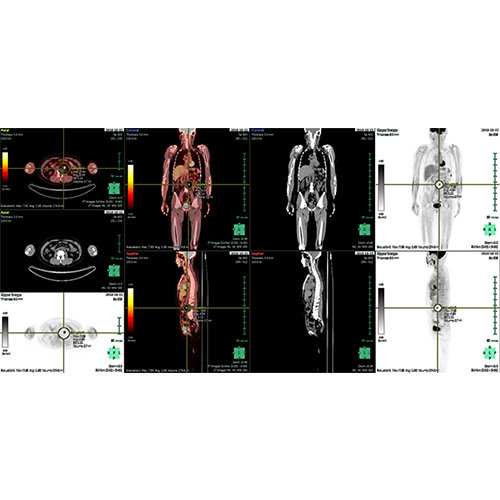

ANYTHINK 经导管主动脉瓣膜置换术分析系统